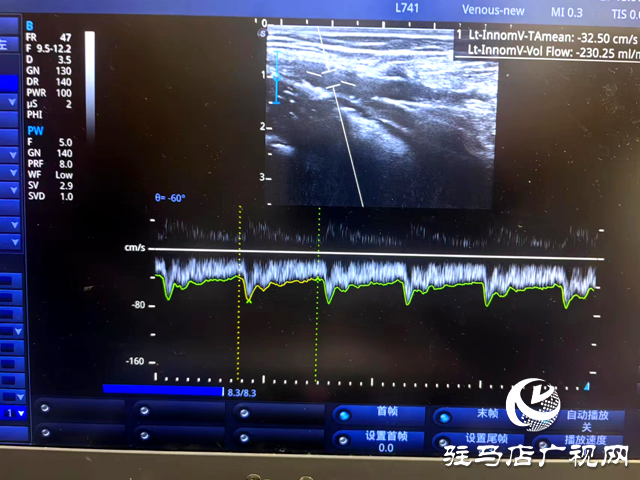

接診后,邱明生主任進(jìn)行了詳細(xì)問診,隨后完善前臂血管彩超。彩超檢查顯示,付女士患有嚴(yán)重的頭靜脈狹窄(內(nèi)膜增生),最窄處內(nèi)徑僅有1.2mm,內(nèi)瘺血流量230ml/min,遠(yuǎn)小于血液透析所要求的流量大于500ml/min。得知這一情況,付女士焦急萬分又無可奈何,“這該怎么辦呢?我已經(jīng)做過兩次擴(kuò)張了!”

術(shù)后,經(jīng)彩超評(píng)估,付女士肱動(dòng)脈血流量由植入前230ml/min擴(kuò)容到638ml/min,支架成功打通了狹窄內(nèi)瘺,建立起透析“生命線”通路。術(shù)后即開始了正常的血液透析治療。